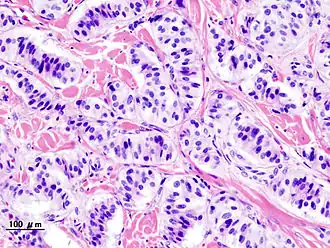

Histopathologie van een insulinoom

Een insulinoom is een neuro-endocriene tumor die uitgaat van de insulineproducerende bètacellen in het pancreas. De bètacellen liggen in de eilandjes van Langerhans. Deze insulineproducerende tumor gedraagt zich autonoom; hij onttrekt zich aan de regelingsmechanismen rondom de glucosespiegel in het bloed. Hierdoor wordt er meer insuline afgescheiden dan vaak nodig is waardoor een hypoglykemie kan ontstaan. Met medicijnen zijn de klachten enigszins te beïnvloeden maar de definitieve oplossing is de chirurgische verwijdering van de tumor.